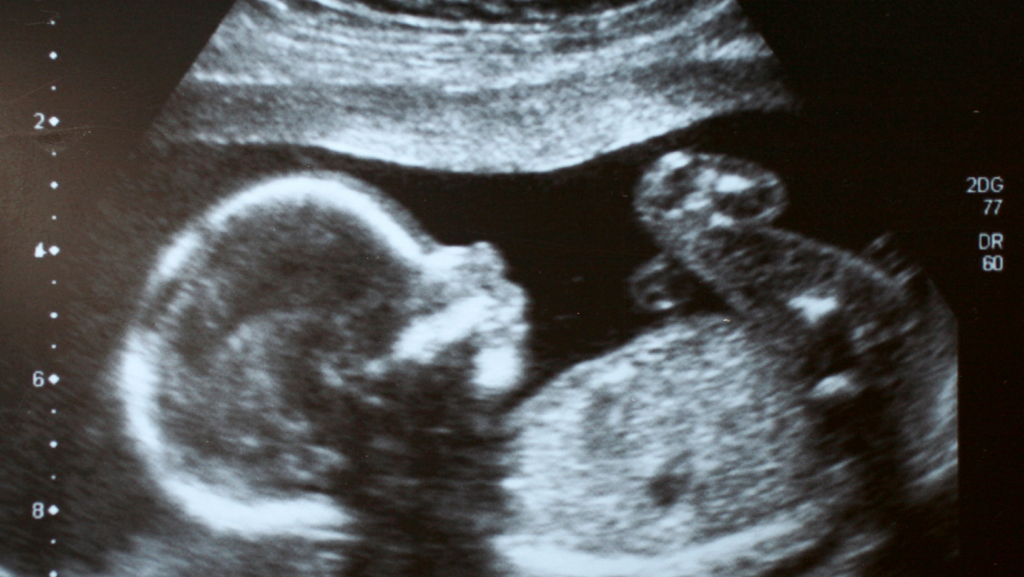

Picture of Heartbeat of Toledo

Heartbeat of Toledo